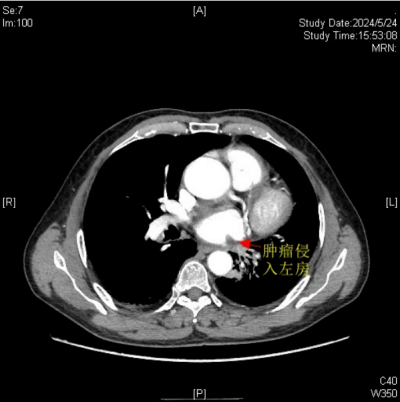

肿瘤侵入左心房

据悉,今年67岁的楚天海(化名)有长达40余年的吸烟史。因反复咳嗽、咯血等症状持续3个月之久,来到长沙市中心医院(南华大学附属长沙中心医院)胸心外科门诊就诊。经全面检查与评估,诊断他患有左肺中央型鳞癌,且肿瘤有部分侵入左心房,情况凶险。

医院胸心外科主任、主任医师袁跃西表示,由于肿瘤侵入左心房,传统手术方式会因为手术视野受限、可能出现难以控制的大出血风险、肿瘤切除可能不彻底及术后恢复难度大等问题,如何确保患者安全并彻底切除肿瘤,成为了摆在医疗团队面前的难题。